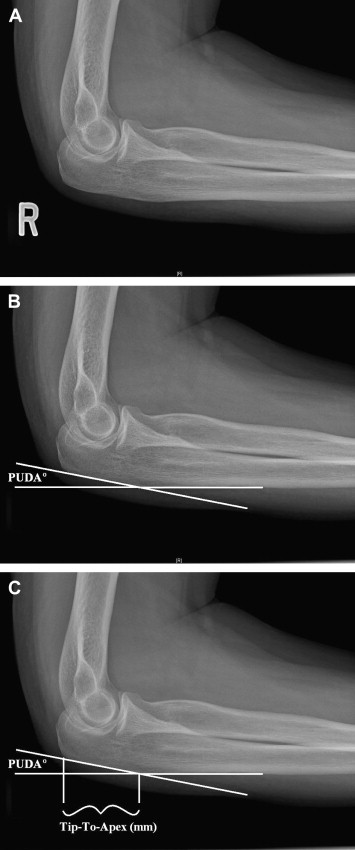

What is the PUDA angle?

PUDA = proximal ulna dorsal angulation